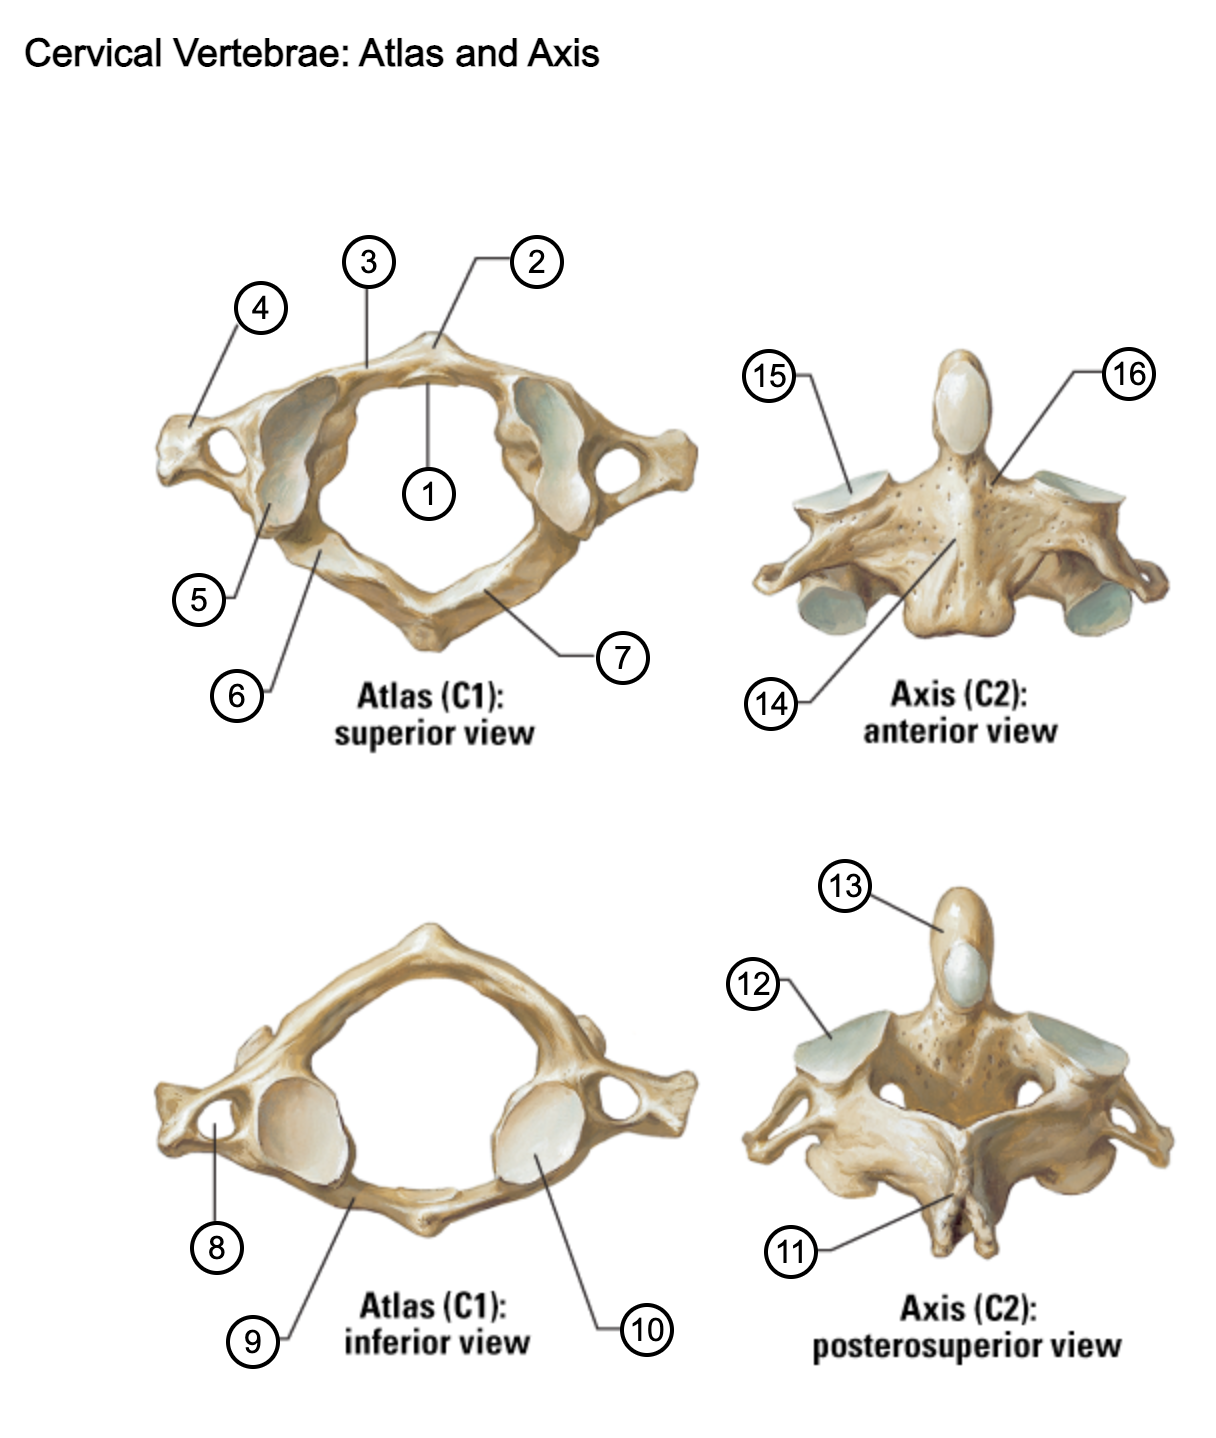

1

facet for dens

2

anterior tubercle

3

anterior arch

4

transverse process

5

superior articular surface of atlas

6

groove for vertebral artery

7

posterior arch

8

transverse foramen

9

anterior arch

10

inferior articular surface of atlas

11

spinous process

12

superior articular facet

13

dens of axis

14

body of axis

15

superior articular facet for atlas

16

pedicle of vertebral arch